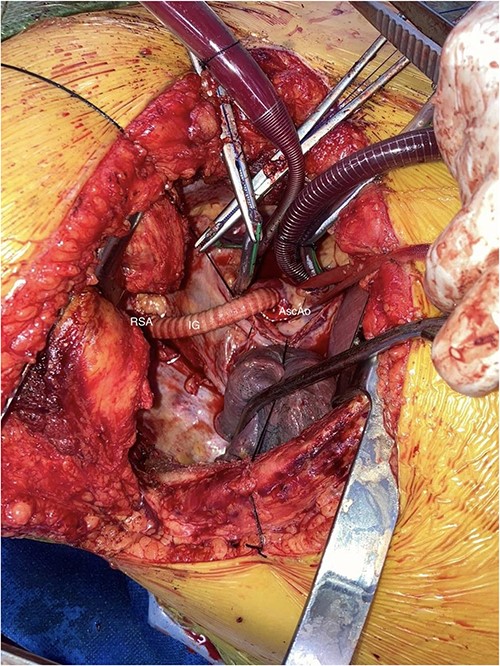

Perfusion pressures were reduced, and a side-biting clamp was applied to the aorta. An 8-mm Vascutek graft was anastomosed to the right lateral aspect of the ascending aorta.

A Covidien vascular stapler was used to divide the aberrant vessel close to its aortic insertion. The vessel was then delivered back behind the esophagus into the right chest. The ARSA was anastomosed (end-to-end) with the Vascutek graft, which had already been anastomosed onto the ascending aorta (Fig. 2).

AscAo: ascending aorta, IG: interposition graft, RSA: right subclavian artery.